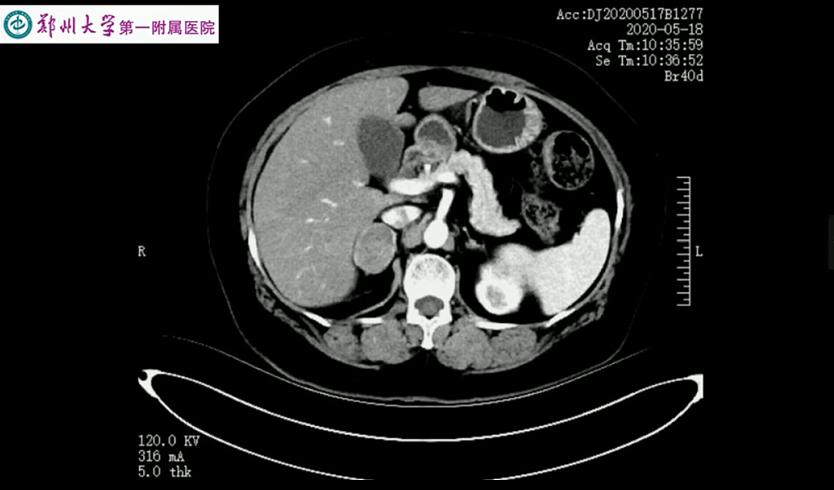

肾上腺肿瘤的下腔静脉瘤栓较为少见,本手术过程中意外发现中央静脉及下腔静脉瘤栓,术中隐约可见瘤栓在下腔静脉里漂荡,可能因瘤栓较细,术前CT难以发现。 由于右侧中央静脉太短,经反复尝试无法通过直接钳夹完整取栓后,术者最终选择切开血管取栓。后腹腔空间小且手术部位位置深,下腔静脉取栓手术难度较高。原则上应阻断瘤栓的近端及远端,但考虑到经后腹腔阻断瘤栓近心端下腔静脉操作困难,难以进行,故选择结扎切断两根肝短静脉、阻断瘤栓远端下腔静脉,然后调高气腹压以对抗减低了的腔静脉压,以达到少出血甚至不出血的目的。 手术演示